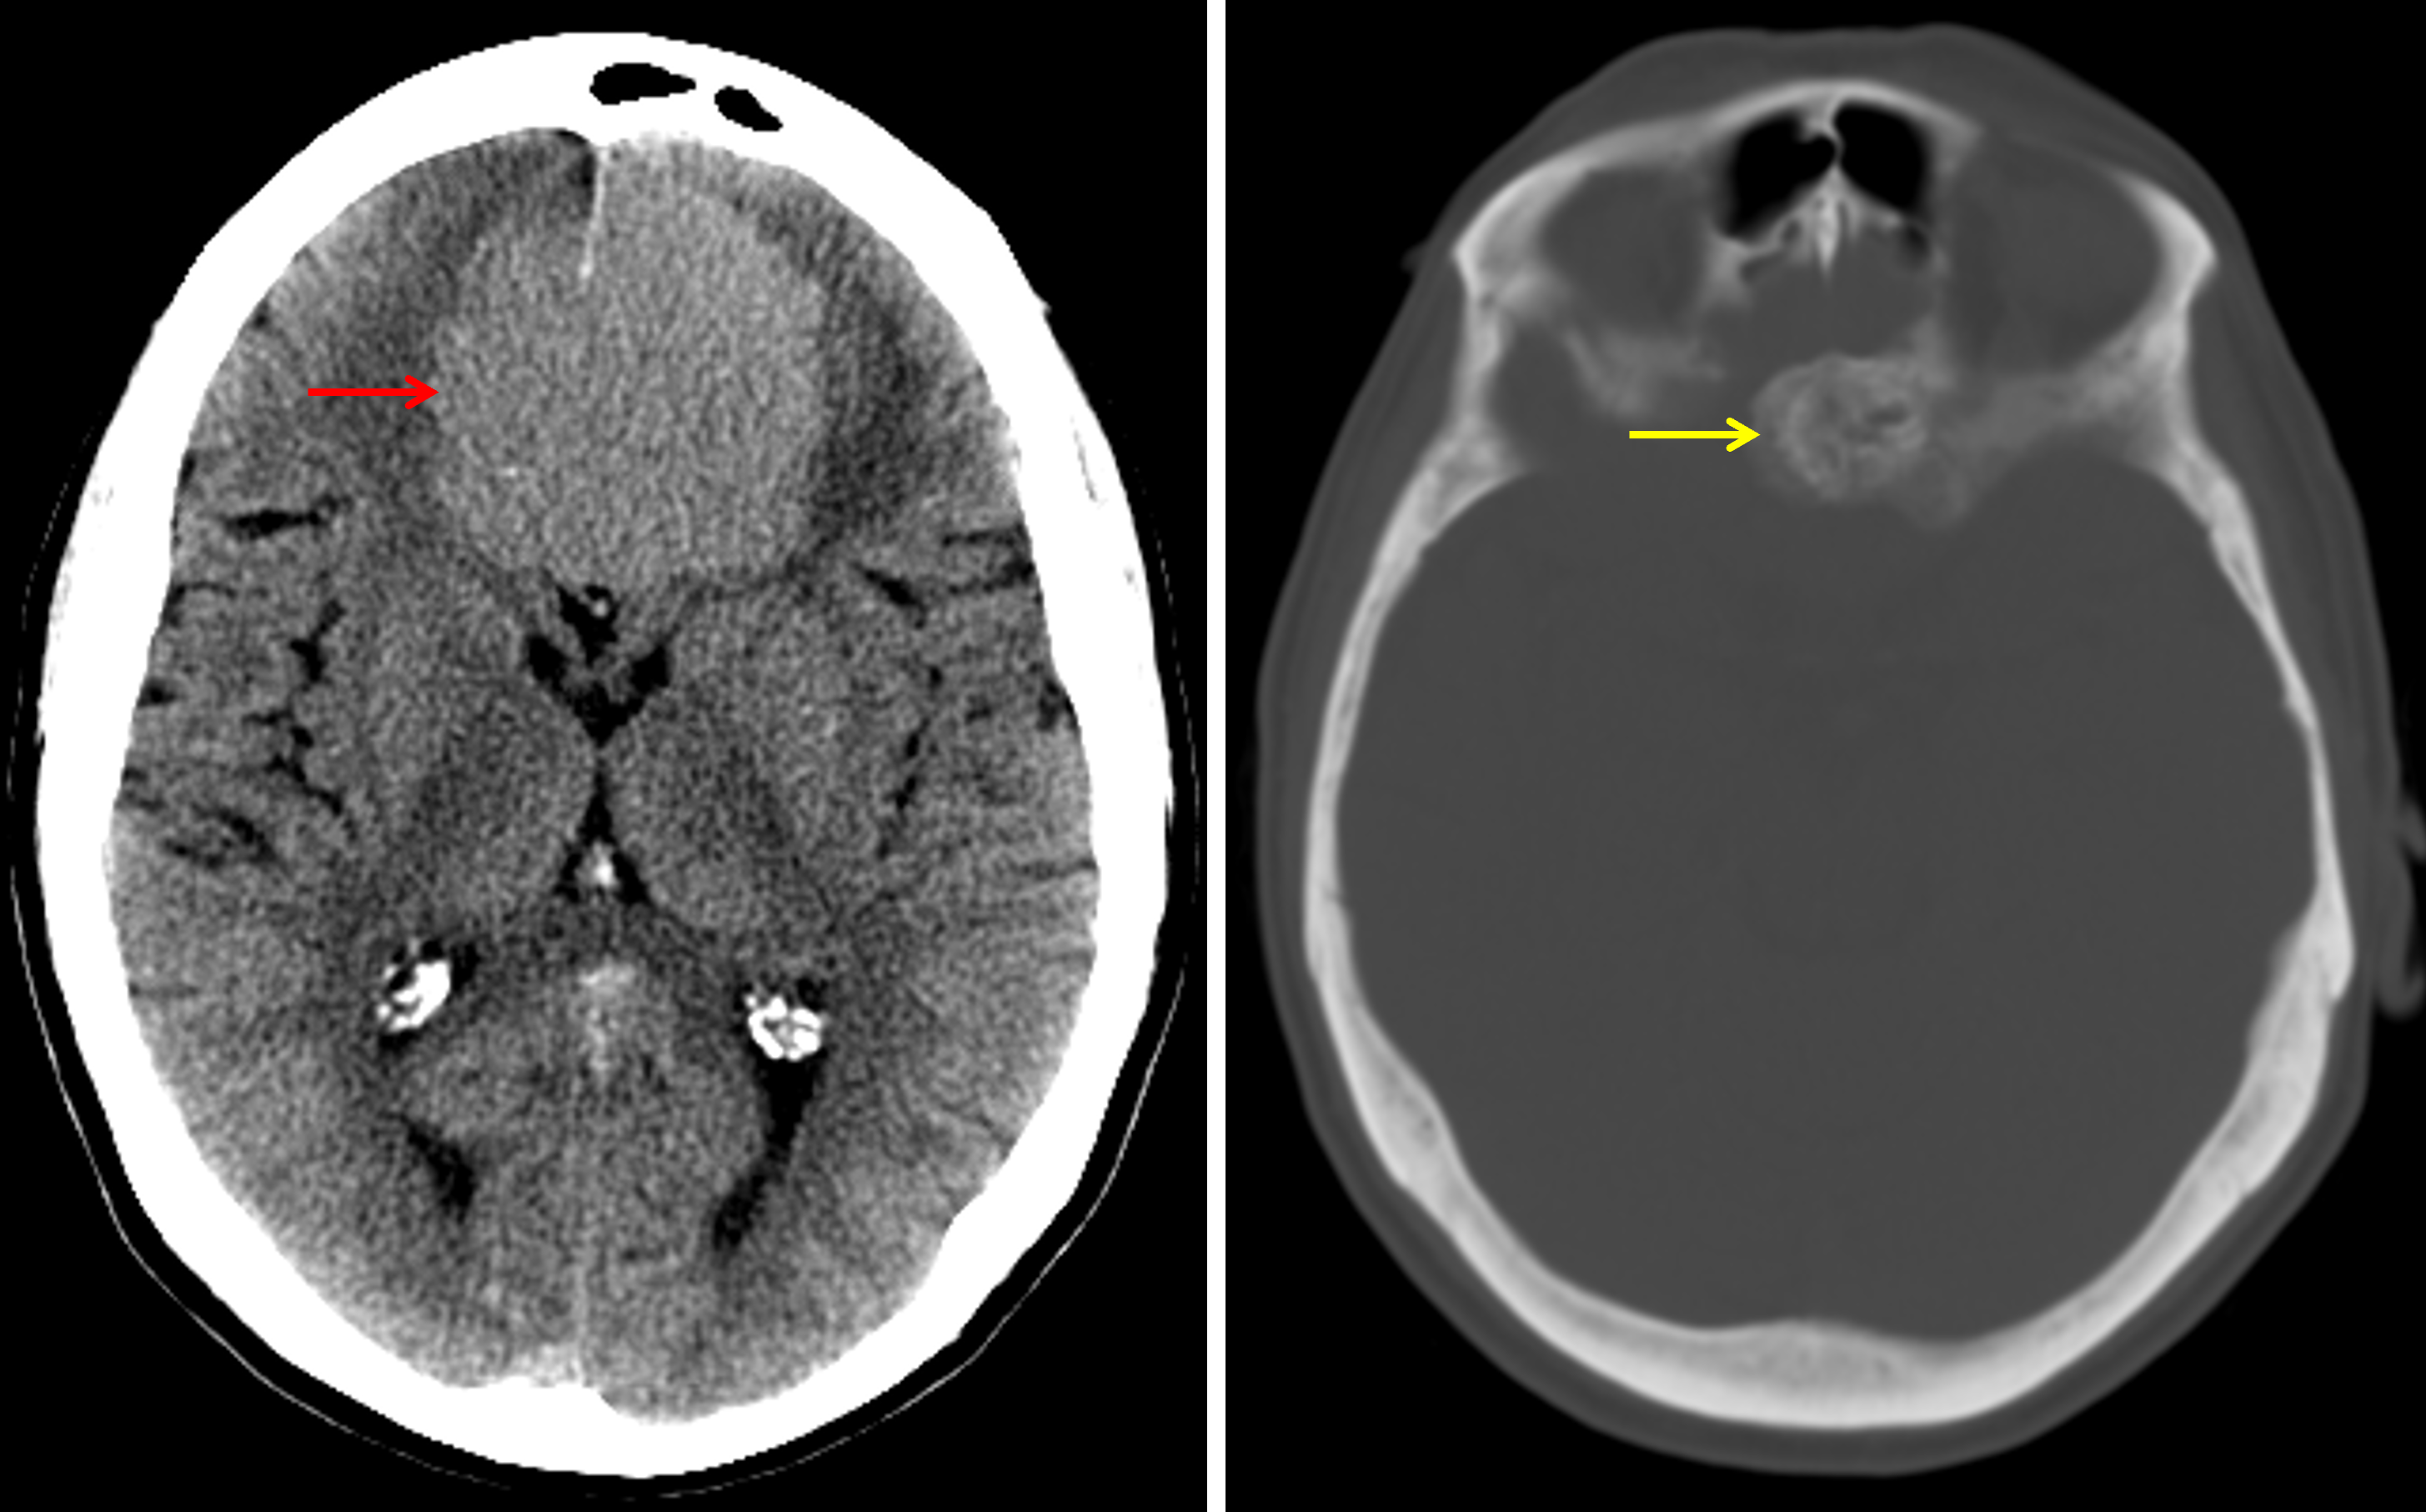

Age: 65

Sex: Female

Indication: Headache

Meningioma